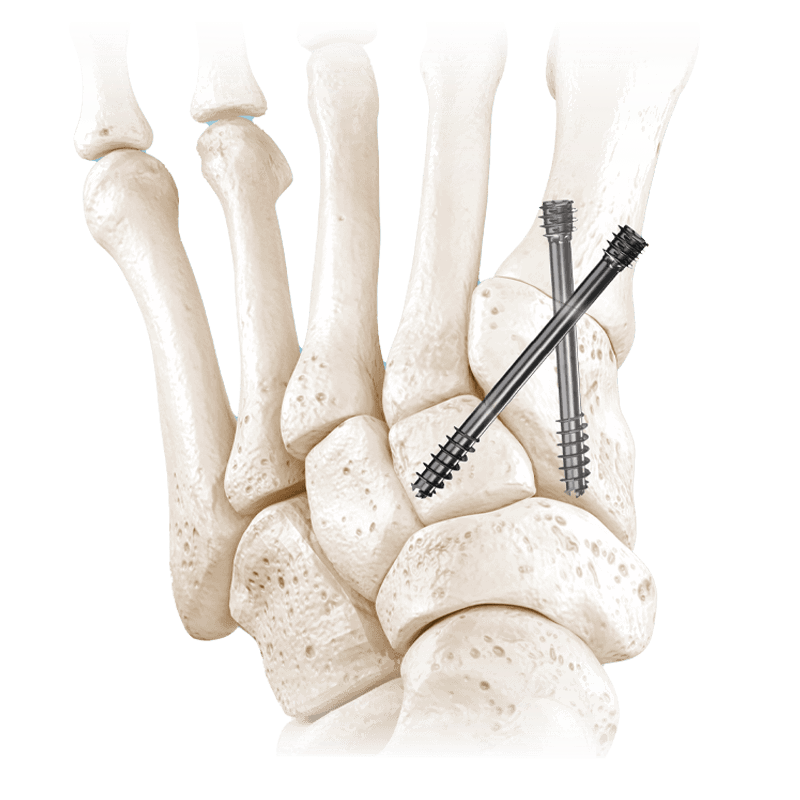

Fixation Devices - Compression Hardware

IBS™-B Beveled Screw System

IBS™-B Beveled Screw System delivers the strength, control, and versatility your MIS workflow demands.